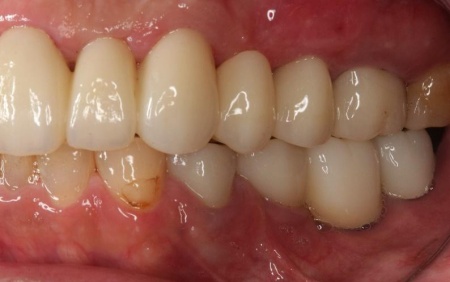

治療後

インプラントが骨にしっかりとなじんだことを確認したら、白くて強度の高い人工歯「ジルコニアクラウン」を装着しました。

左下奥歯1本、右下奥歯2本に装着されていた古い被せ物はすべて外し、ジルコニアクラウンと交換しました。